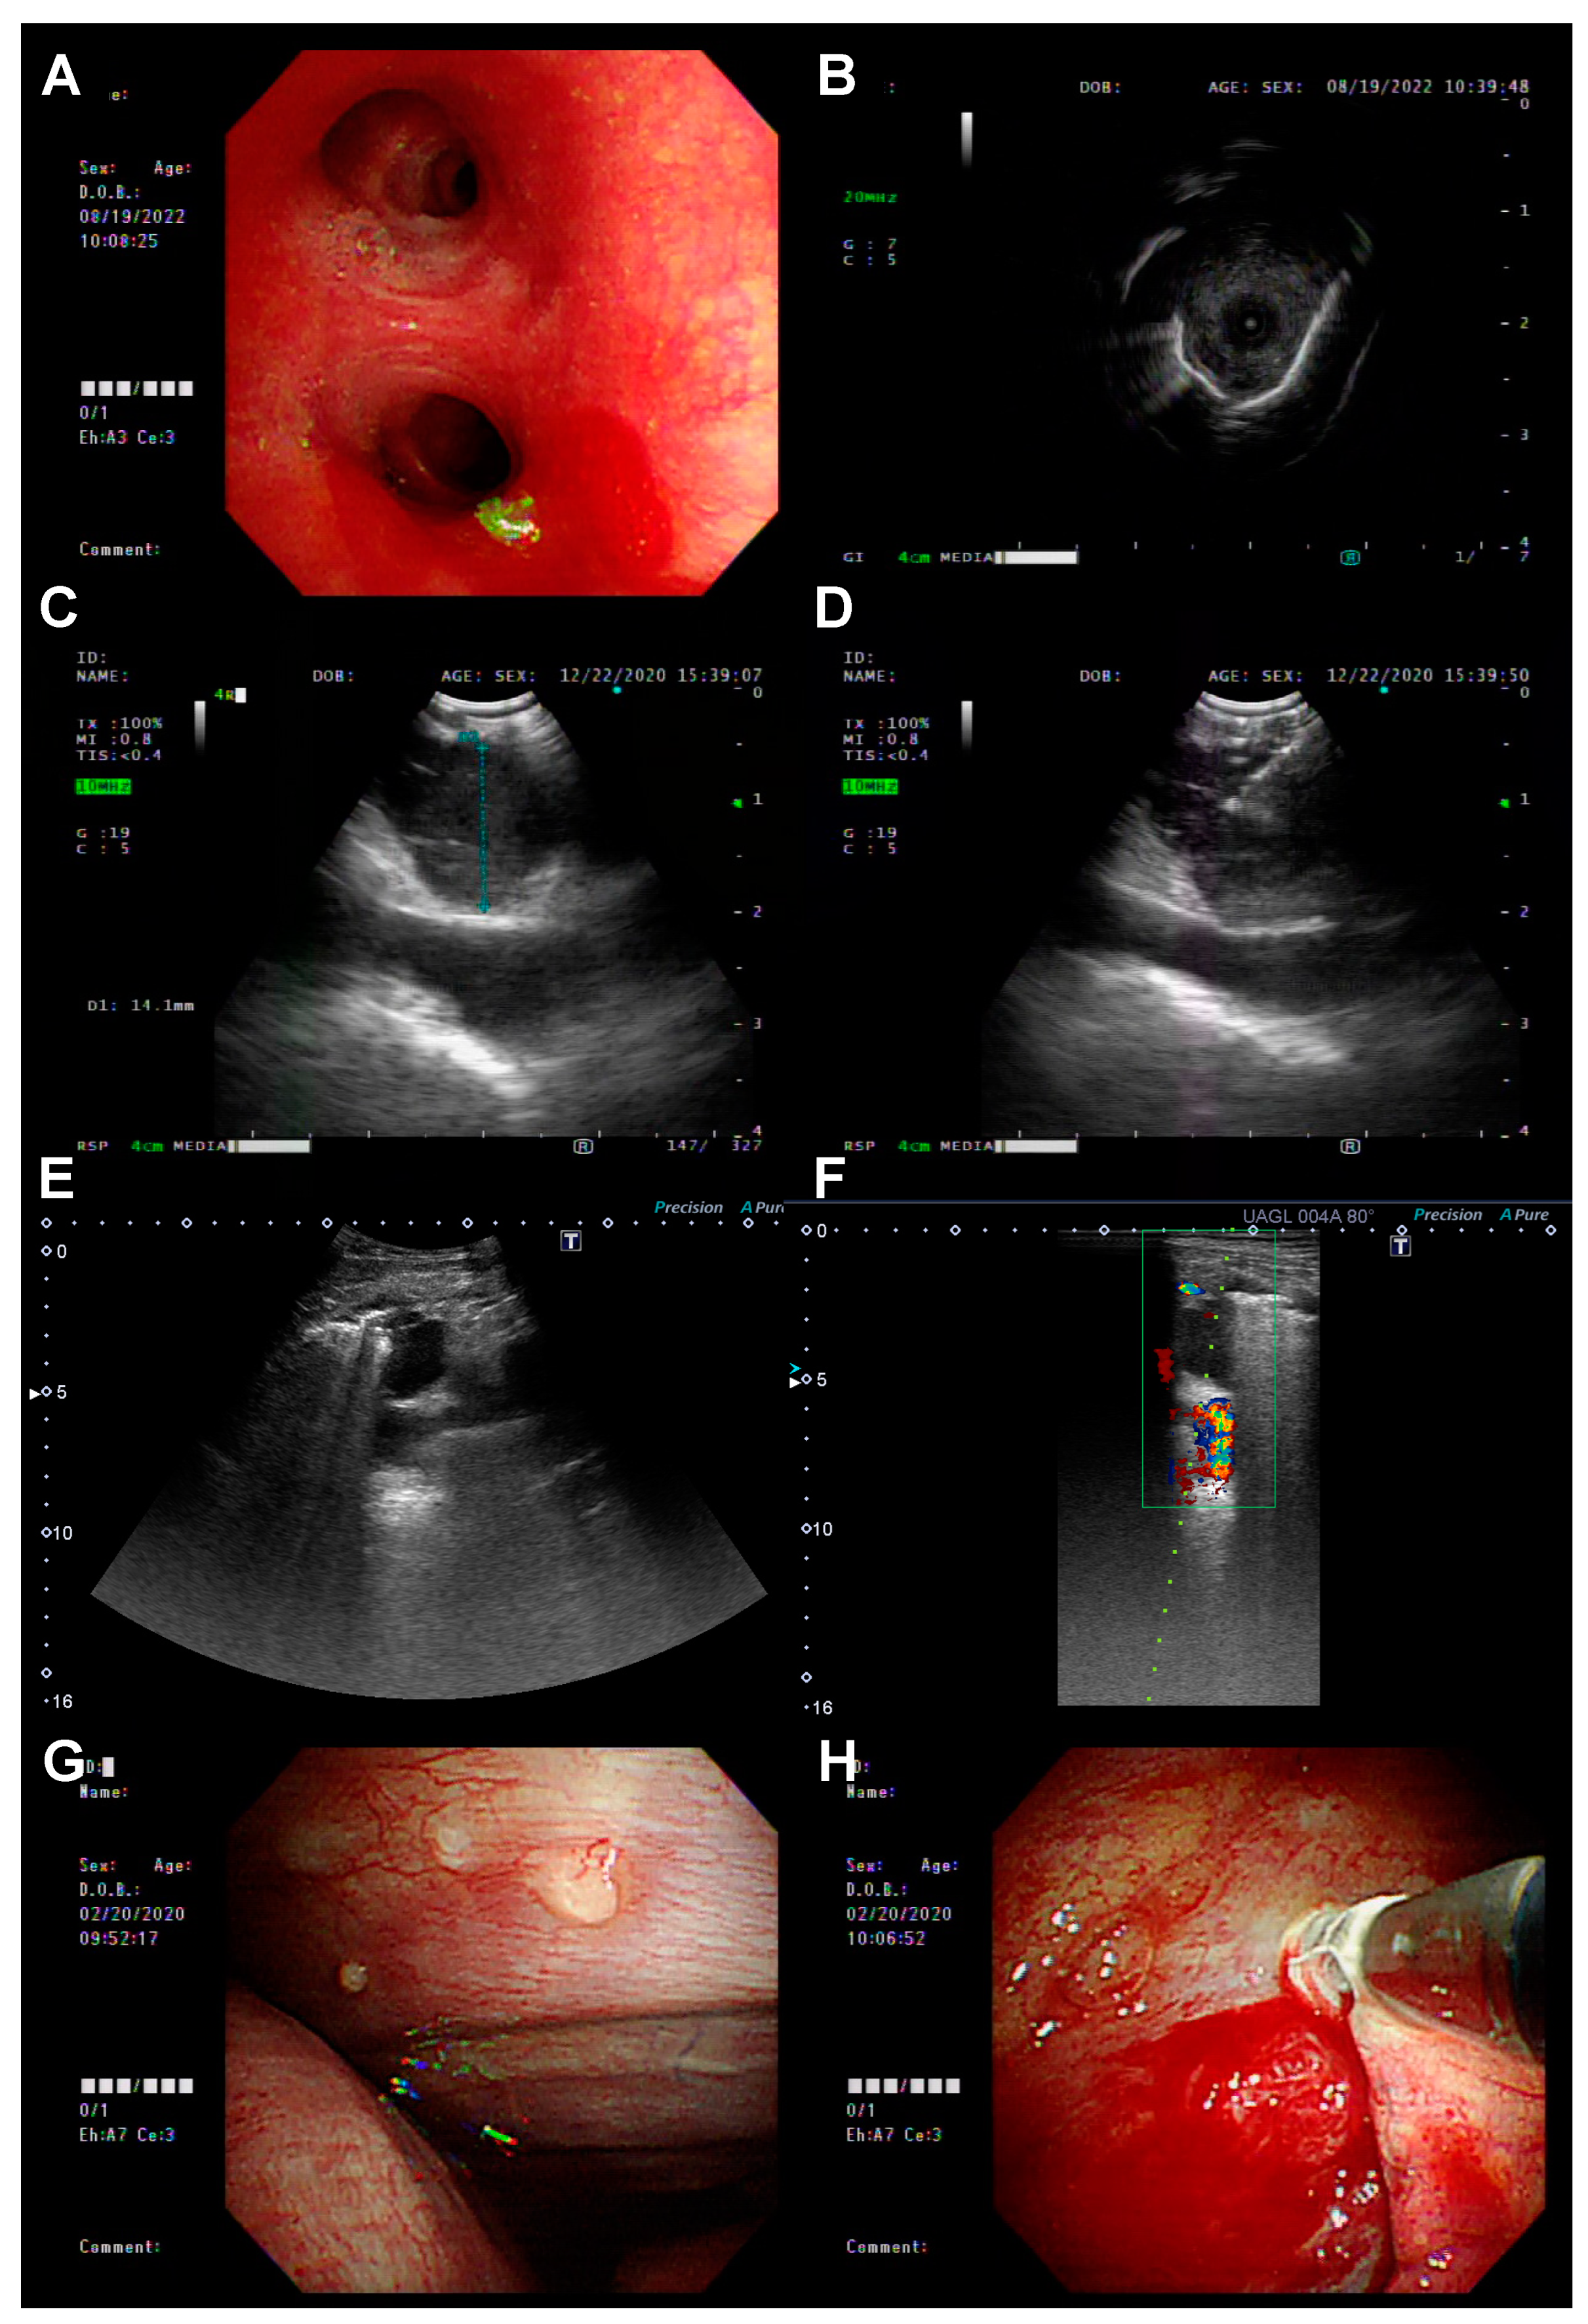

2.2. Re-Biopsy Methods and EGFR T790M Mutation Testing

3.2. The Biopsy Tissue Assessment and Diagnosis by Different Biopsy Methods

3.3. The Biopsy Tissue Molecular Analysis by Different Biopsy Methods